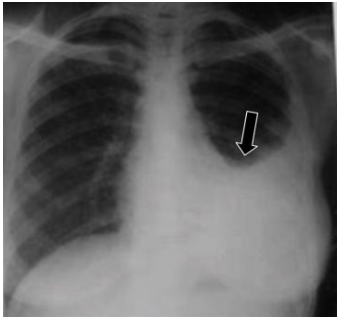

21

Q

o que é visto nesse raio-x

A

tuberculose primária apresentando derrame pleural